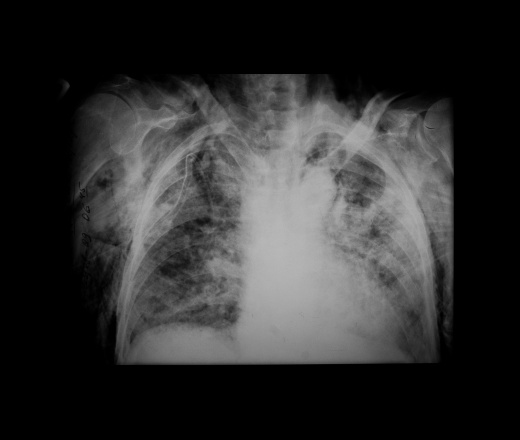

Воспалительный инфильтрат — описание болезни

Симптомы болезни Воспалительный инфильтрат

Воспалительные инфильтраты возникают как за счет контактного распространения инфекции (per continuitatum), так и лимфогенного пути при поражении лимфатического узла с дальнейшей инфильтрацией тканей. Инфильтрат обычно развивается в течение нескольких дней. Температура у больных бывает нормальной и субфебрильной. В области поражения возникают припухлость и уплотнение тканей с относительно четкими контурами и распространением на одну или несколько анатомических областей. Пальпация безболезненная или слабо болезненная.

Флюктуация не определяется. Кожные покровы в области очага поражения обычной окраски или слегка гиперемированы, несколько напряжены. Имеет место поражение всех мягких тканей данной области — кожи, слизистой оболочки, подкожно-жировой и мышечной ткани, нередко нескольких фасций с включением в инфильтрат лимфатических узлов. Именно поэтому мы отдаем предпочтение термину «воспалительный инфильтрат» перед термином «целлюлит», которым также обозначают подобные поражения. Инфильтрат может разрешаться в гнойные формы воспаления — абсцессы и флегмоны и в этих случаях его следует рассматривать как предстадию гнойного воспаления, которую не удалось купировать.

Диагностика болезни Воспалительный инфильтрат

Дифференциальную диагностику воспалительного инфильтрата проводят с учетом выявленного этиологического фактора и давности заболевания. Диагноз подтверждают нормальная или субфебрильная температура тела, относительно четкие контуры инфильтрата, отсутствие признаков гнойного расплавления тканей и резкой болезненности при пальпации. Другими, менее выраженными, отличительными признаками служат: отсутствие значительной интоксикации, умеренная гиперемия кожного покрова без выявления напряженной и лоснящейся кожи. Таким образом, воспалительный инфильтрат может характеризоваться преобладанием пролиферативной фазы воспаления мягких тканей челюстно-лицевой области. Это, с одной стороны, свидетельствует об изменени реактивности организма ребенка, с другой — служит проявлением естественного и терапевтического патоморфоза.